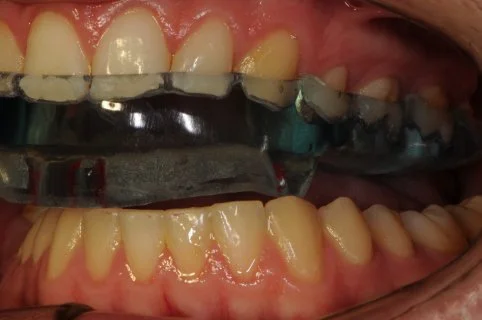

A TMJ Disorder patient requires conservative management with “Full Occlusal Therapy” in 3 stages along with concurrent Full Counselling (refer to journal papers 19 and 20).  In other words, we need to get the disc back into the centre of the joint where it belongs starting with Full Counselling and then a Fully Protective Occlusal Splint (Stage 1).  This splint is made of acrylic resin (used for dentures) and can be made in clear resin but is usually coloured blue or pink to hide any future discolouration (as in the photos below). The splint usually fits the upper teeth and only one is required.

Stage 1 - Fully Protective Occlusal Splint - 4 SA’s over a 3 month period

Stage 1 of Full Occlusal Therapy is Formal Fully Protective Occlusal Splint Therapy with case study